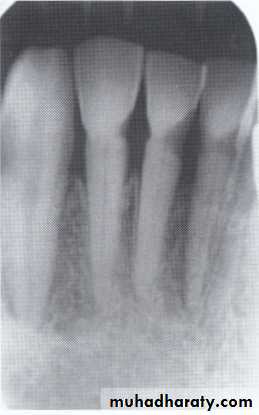

* Hutchinson’s Incisor

lateral incisors are peg-shaped or screwdriver-shaped.

widely spaced.

notched at the incisal edge.

with a crescent-shaped deformity